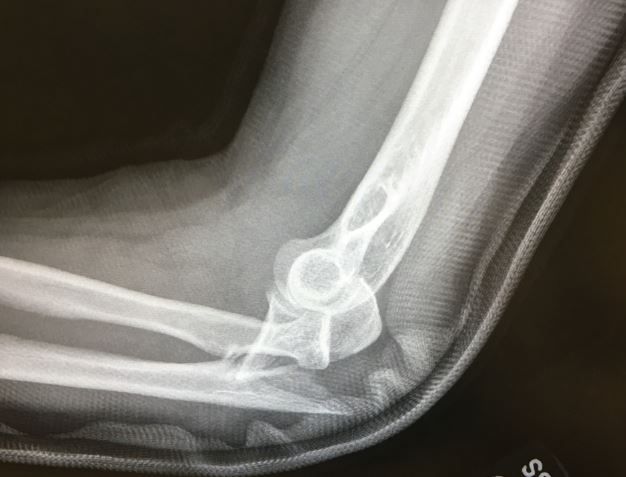

A 20-something young man is in the ED after a fall off a scooter while doing tricks. What do you see on the x-ray? What type of injury is it?

Patient history. A man in his 20s presents to the emergency department (ED) for elbow pain and deformity after a fall from a scooter while doing tricks. He denies any neck or back pain or other complaints and was wearing a helmet but no elbow pads or other protective gear.

Relevant test results. Imaging, below.

What is the most likely diagnosis?